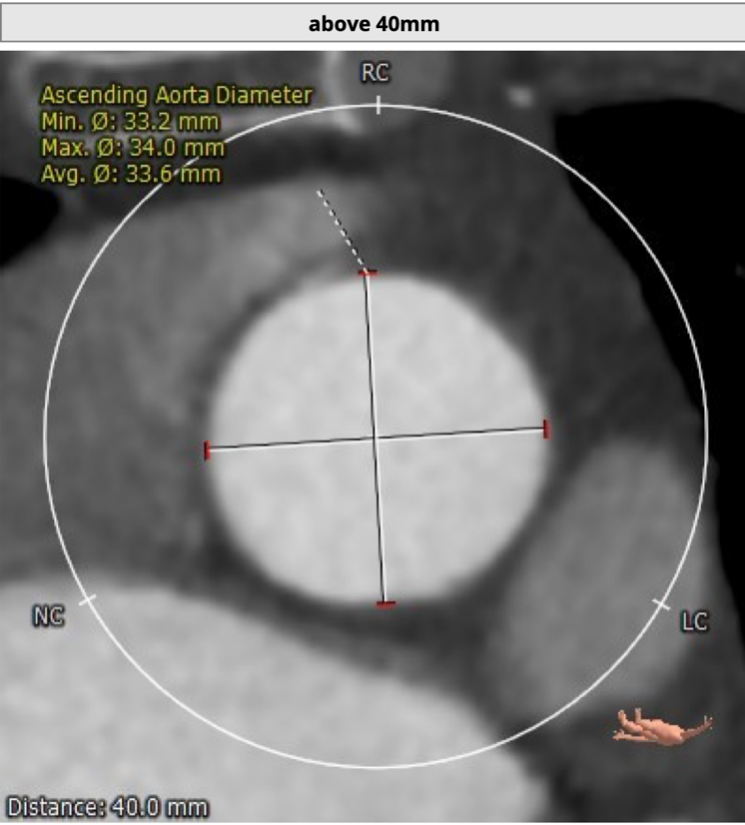

患者为73岁老年男性。CT评估显示其为三叶瓣,伴有轻度钙化,双冠高度可,升主动脉未见明显增宽,主动脉弓部角度平缓。瓣环最短径为17.6mm,最长径为24.7mm,平均瓣环直径为21.1mm。升主动脉平均直径33.6mm。左冠开口高度12.0mm,右冠开口高度14.2mm,冠脉阻塞风险低。外周血管未见明显钙化,最窄处直径为5.7mm。入路情况较佳。

升主动脉